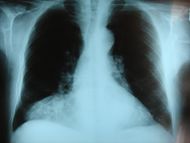

Frontal chest X-ray showing a hernia of Morgagni | |

الفتوق التي لا تظهر للعيان

أهمها نوعان: الفتق الحجابي بين البطن والصدر، وفتق النواة اللبية في العمود الفقري.

الفتق الحجابي

مقالة مفصلة: الفتق الحجابي

الفتق الحجابي diaphragmatic hernia، من الناحية التشريحية هو صعود جزء من المعدة (عادة منطقة القاع العلوية) من البطن إلى الصدر عبر الفوهة الطبيعية الموجودة في الحجاب الحاجز، والتي يمر فيها المري من الصدر إلى البطن بسبب اتساعها أو بسبب ضعف في آلية تثبيت المعدة وخاصة منطقة الفؤاد ضمن البطن.